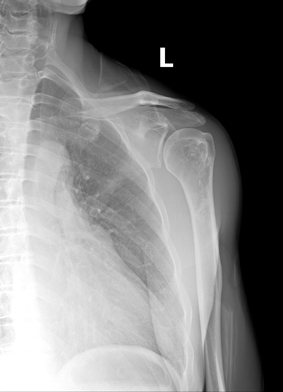

男,50岁,左肩部轻微疼痛,活动不便5个月就诊,无红肿热痛,间断理疗治疗无好转,既往5个月前左肩轻微拉伤史。

肱骨上段髓腔内蜿蜒索条状、簇状高密度影,肱骨头多发囊变。考虑:肩关节周围炎,并肱骨上段骨梗死。

支持骨梗死的诊断,但平片不好诊断,结合临床考虑是肩周炎。但诊断应该是临床诊断的